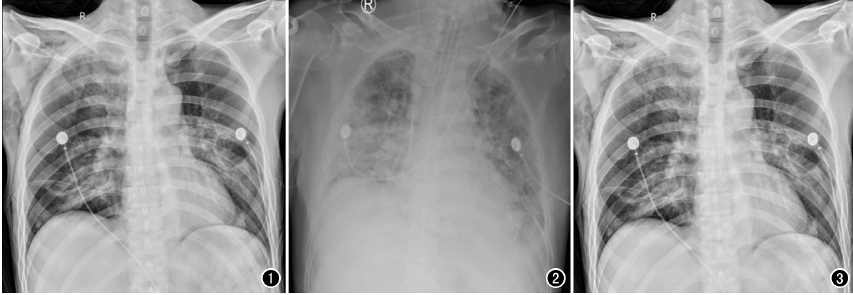

以心臟手術為例,開胸心臟手術多數(shù)是在低溫、全麻和體外循環(huán)下進行,胸腔創(chuàng)傷較大、風險極高,心臟術后,心外科醫(yī)師為了能及時了解術后患者的雙肺復張情況、氣管插管導管頭端位置以及手術并發(fā)癥等情況,需要及時對患者進行胸部X線片檢查,以便觀察氣管插管位置,一般來說,插管位置下端應位于第3胸椎水平,過深或者過淺都將影響呼吸機的輔助效果,應確保位置準確,以免影響通氣狀況。另外,包括對于相關手術并發(fā)癥的檢查,包括:胸腔積液、氣胸、肺不張等常見問題,需要及時進行胸部X光檢查。相較于幾百萬像素的移動DR,百微移動DR,在圖像質量上顯示更清晰,檢查效率更高,更利于醫(yī)生及時進行處置。